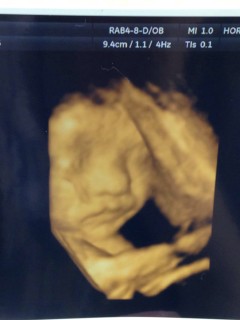

32w2d1705gの男の子です! 今日はとても綺麗に撮れたと先生にも看護師さんにも誉めて頂きました(´∀`) 丸い鼻は私似かな?笑 早く会いたいよー※。.:*:・'°☆